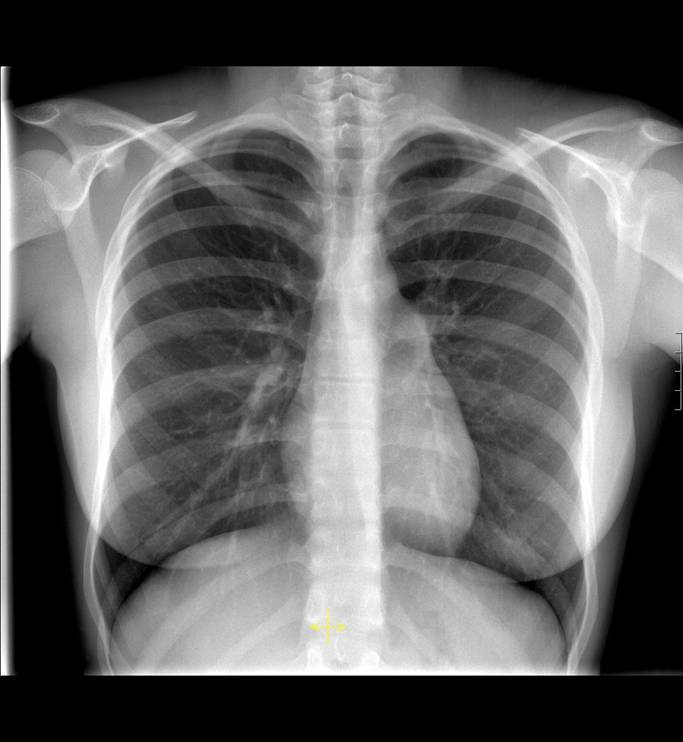

3. RADIOGRAFÍA DEL TÓRAX

1. Recomendaciones

1. Permanecer en posición ergida

2. Imagenes Negras en placa fotográfica

1. Contraindicación

1. Embarazo

2. Visualización

1. Sombras anormales- Líneas Invasivas- Cuespos externos